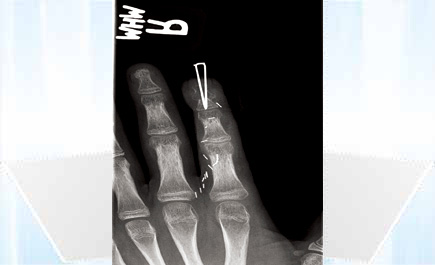

بيروت - الجزيرة: نجح فريق جراحي من مركز الامتياز في جراحة اليد، في المركز الطبي في الجامعة الأميركية في بيروت، في إنقاذ سبابة فتى في الخامسة عشرة من العمر من البتر بعد أن تهشمت في حادث انفجار بعض المفرقعات، وقد رممها الفريق باستعمال أصبع من أصابع قدم الفتى. وقال الدكتور يوسف